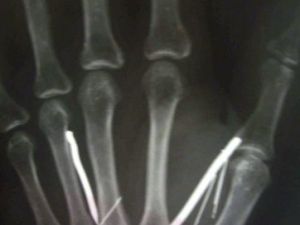

صورة اشعة ليد الخادمة السريلانكية تظهر وجود مسامير

سعودي يحمي مسامير ويغرسها بجسد خادمته السريلانكية